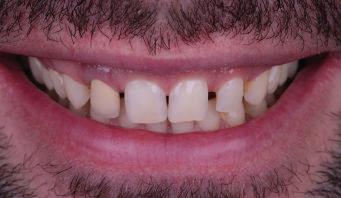

Пациент: 30 г., мъж Първо посещение: 02.08.2018 г. Основни оплаквания: Лицева болка, главо болие и болка в дясната темпоромандибу ларна става, естетични съображения РАБОТЕН ПРОТОКОЛ:

Пациентът постъпи в моята клини ка с наличие на темпоромандибуларен дисфункционален болков синдром, едно странно изместен диск с редукция в дяс ната става, клас II, подклас 2, тесни гор на и долна челюст със струпване, дъл бок овърбайт

6 Dental Tribune Bulgarian Edition / октомври 2022 г. КРАТКО ОПИСАНИЕ НА КЛИНИЧНИЯ СЛУЧАЙ

оклузална равнина ендодонтски проблеми – 15, 25, 35, 36, 37, 45, 46, 47 отклонение на срединната линия с 2 мм вляво в долна челюст мускулни болки ДИАГНОСТИКА: скелетен клас II зъбен клас II функция: ограничения в движенията –мускулни проблеми; хлабави лигамен ти – латеротрузивни странични про блеми при медиотрузия вдясно; девиа ция на долната челюст вляво. ЦЕЛИ НА ЛЕЧЕНИЕТО: разширяване на горната и долната зъбна дъга промяна на оклузалната равнина в по сока надолу – намаляване на наклона на оклузалната равнина, така че да стане по-плоска, и постигане на пра вилна оклузална равнина дистално намаляване на вертикалния размер на оклузията (LFH)

и гингивална усмивка. Започнахме лечението с пълна диагно стика (анамнеза, интраорални, екстра